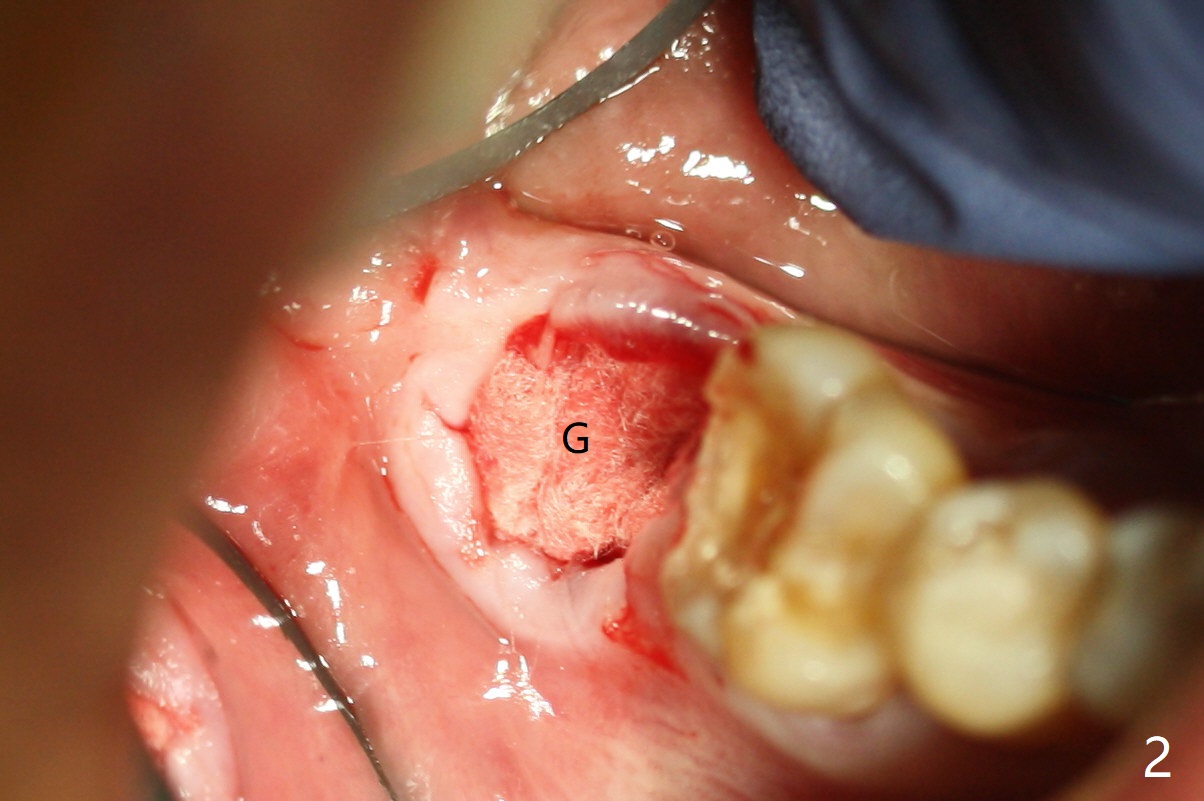

The residual roots of the tooth #31 are lower buccal (Fig.1 B), which in fact is molded and worn by the supraerupted tooth #2. When the tooth is extracted (Fig.2) and an implant, abutment (Fig.3 gold colored) and allograft (*) are placed, the abutment has to be trimmed. An atypical immediate provisional is fabricated by spreading setting acrylic over the abutment and bone graft (Fig.4 P) with occlusal equilibrium. Advantages of the guided surgery are good position (Fig.3 buccolingual), trajectory and depth (Fig.5,6) of the implant. The buccodistally exposed implant threads are packed with allograft in sufficient amount (Fig.3,5,6 *). The atypical immediate provisional breaks down and dislodges 3 weeks postop (Fig.7). In fact the implant plateau is exposed buccally. A monojet is given to the patient for self cleansing. He is instructed to return in 3 weeks. The exposed implant threads are covered 1.5 months postop (Fig.8). Incomplete abutment seating (Fig.9 <) was not noted until 1 year 3 month post cementation when the crown was mobile (Fig.10). A 6x3 mm healing abutment is placed. Three days later, the crown is sectioned and separated from the abutment. The latter returns to place; due to angulation associated with PA, the gap between the implant and abutment is indistinct (Fig.11). Bitewing is taken; the gap exists (Fig.12 <). The abutment seems to be seated deep; there is apparently soft tissue interference. A 5.2x4(2) mm abutment remains incompletely seated (Fig.13 >). A 5.2x4(3) mm one is completely seated (Fig.14 <). Zirconium crown with an access hole is cemented in the mouth. The crown and abutment is then removed for residual cement removal and reseated and torqued (Fig.15). Four months later, the Zirconium crown is fractured (Fig.16). Impression is retaken for high noble metal crown without access hole for strength (Fig.17).